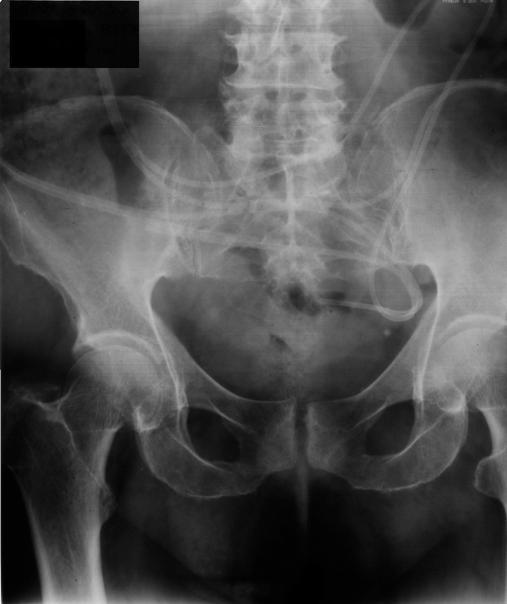

Two patients with ventriculoperitoneal shunt catheter (V-P shunt) were admitted to our unit during the last year. They previously had a shunt catheter implanted for hydrocephalus of unknown cause. The complete migration of the ventriculoperitoneal shunt catheter into the peritoneal cavity was observed in these patients 12 and 7 years after the implantation. The laparoscopic removal of the migrated catheter was decided on. Its presence and location were confirmed by the use of a 0-degree laparoscope, through a 10-mm trocar port. The catheter was held and pulled out using a grasping forceps that was pushed in just beside the trocar port.

https://cdn.ncbi.nlm.nih.gov/pmc/blobs/dce3/3148885/44317191dbd3/jls0021127430001.jpg